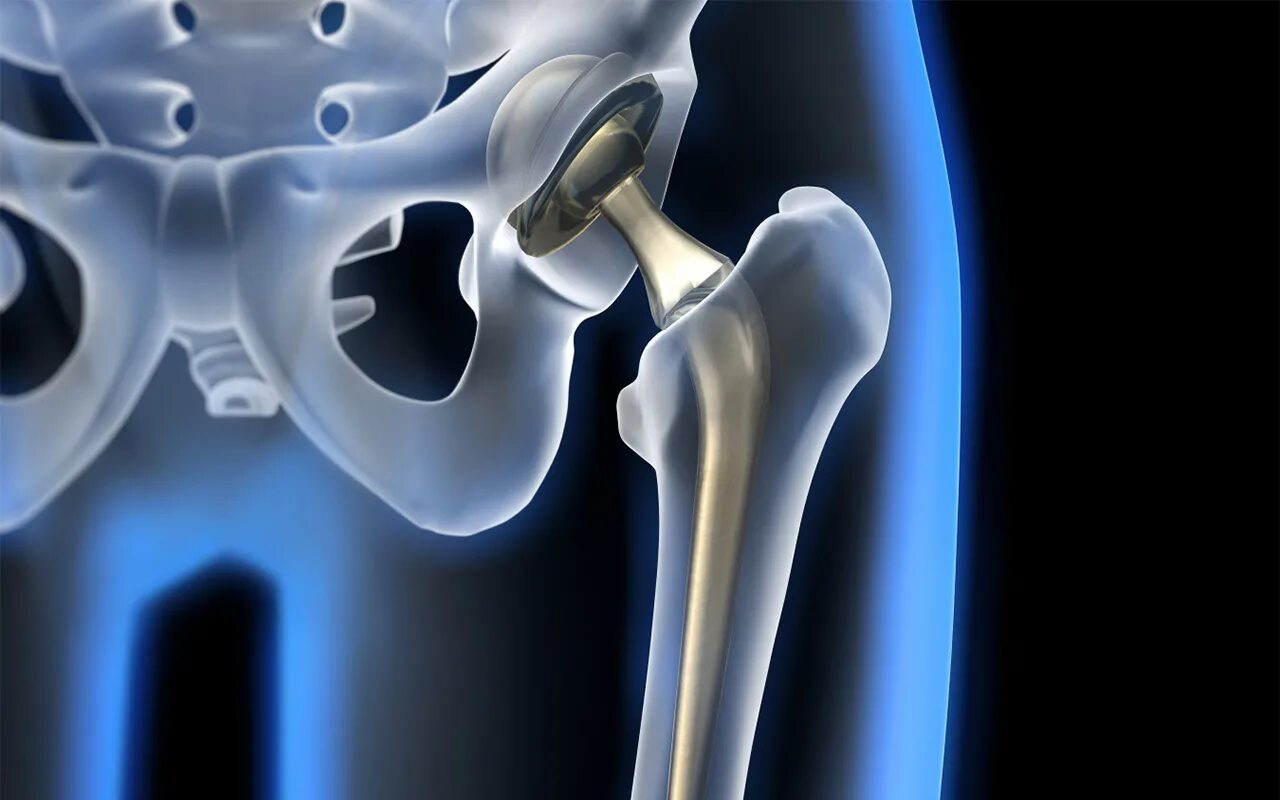

Тазобедренный сустав это